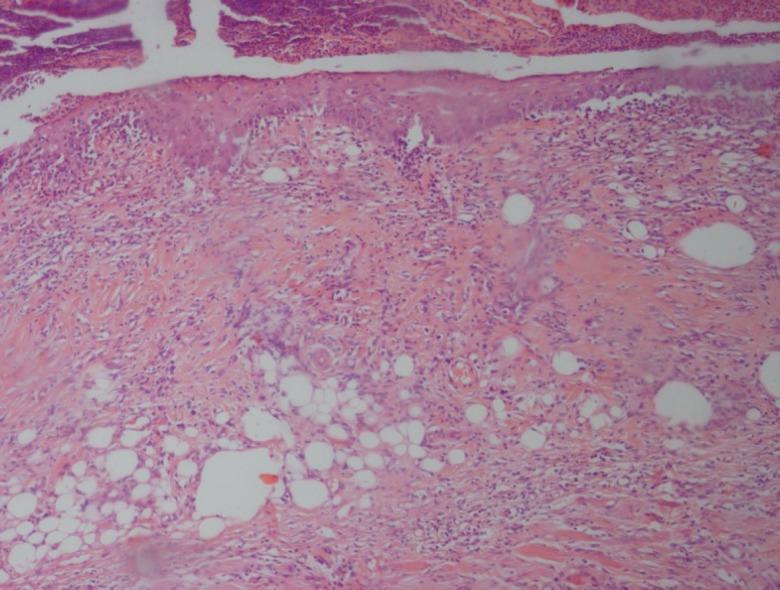

One hundred and twenty female Sprague-Dawley rats were randomly allocated to 4 equal groups. Group A received silver sulfadiazine ointment, Group B received 10% licorice extract and Group C was considered as control group and received gel base as the base of medication. Group D did not receive any medication and just underwent burn injury. A standard 3rd degree burn wound was produced by a hot plate with similar size about 20% of total body surface area (TBSA) and at identical temperature. After 24 h of burn production, 10(8) colony forming units (CFU) of toxigenic strains of P. aeruginosa (PA 103) were inoculated subcutaneously into the burnt area. After 3, 7, 14, 21 and 28 days of therapy, the animals were sacrificed and burn areas were macroscopically examined and histologically evaluated.

Decrease in size of the burn wounds, in inflammation and re-epithelialization were poor in groups B-D. Infection to P. aeruginosa was still visible in groups B-D but was absent in Group A. The mean histological score, tensile strength, maximum stress, yield strength and stiffness in groups B-D were lower compared with Group A.

Licorice extract in 10% concentration was shown not to be effective in healing of P. aeruginosa infected burn wounds.